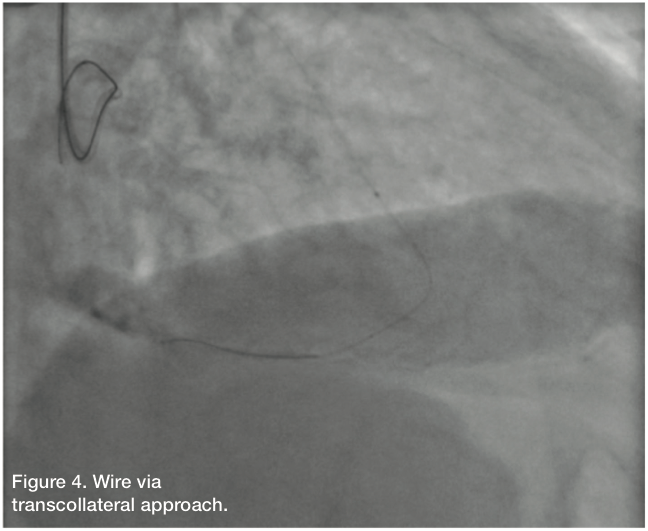

Giving the patient’s angiographic findings, we elected to intervene on the RCA. We upsized the sheath to a 6 Fr Glidesheath in the right radial artery and used an Amplatz left (AL) 1 guide catheter to engage the RCA. We accessed the left radial with a 5 Fr for a contralateral injection and used a 5 Fr JL4 guide catheter from the left radial. Bivalirudin (Angiomax, The Medicines Company) was administered, and using a 1.25 mm over-the-wire balloon and an Asahi Fielder wire (Abbott Vascular), we attempted to navigate the RCA. The wire kept deflecting into a side branch, although there seemed to be, at least on initial angiography, a “beak.” The wire continued to deflect into a side branch. Additional wires were then used, including a Pilot 150 wire (Abbott Vascular) and a Miracle Bros 3 wire (Abbott Vascular), both of which were unsuccessful. At this time, we elected to attempt a retrograde approach via a transcollateral. Left to right collaterals from the circumflex appeared to offer the most direct path. We wired into the LCX artery, but there was poor visualization trying to inject around the 5 Fr sheath. Therefore, we pulled everything, and upsized to a 6 Fr JL4 guide catheter.

Using a Fielder wire and a 1.25mm balloon, we attempted to cross through the septal. However, we could not find an adequate collateral via selective injection of the septal. We then went back to the circumflex artery using a Pilot wire and a 1.25mm Sprinter balloon (Medtronic). Initial attempts were unsuccessful; however, after selective injection through the balloon, an ideal channel was located and successfully navigated. In an attempt to advance the balloon, the guide and guidewire popped out, secondary to poor guide support. We were able to recross into the distal posterior descending artery (PDA). This was confirmed by selective angiogram after advancing the 1.25mm balloon through the collateral into the distal RCA. We exchanged for a Miracle Bros wire and tried to navigate the RCA in retrograde fashion. This was unsuccessful. We then took a Pilot wire, and with the Pilot 200, we were able to navigate the RCA in retrograde fashion. We snared the wire and externalized it in the right radial artery. This did result in fracture of the distal wire tip while trying to externalize it. However, the fracture took place in the right radial sheath and was easily managed.